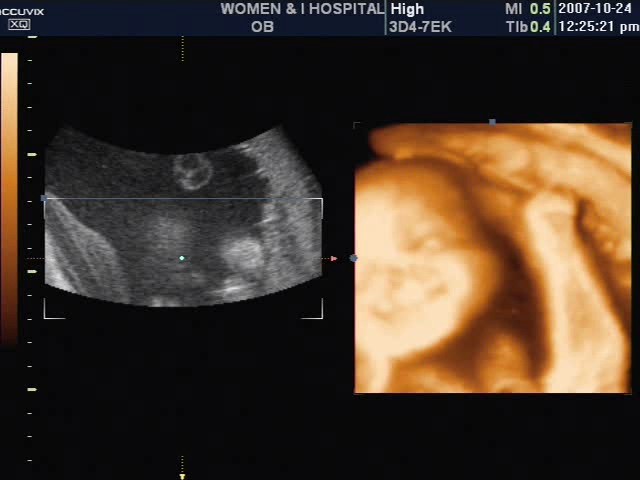

감사하다는 말을 이제야 드리네요... 포기했었는데 지푸라기라도 잡는 심정으로 조이맘을 다니고 첫 시험관아기에서 임신에 성공해 지금 37주가 되어가네요..

12월 17일 울 둥이들을 만날수 있게 됐어요.. 아들 둥이구요.. 36주에 몸무게가 2.7, 2.5 너무 건강하데요...